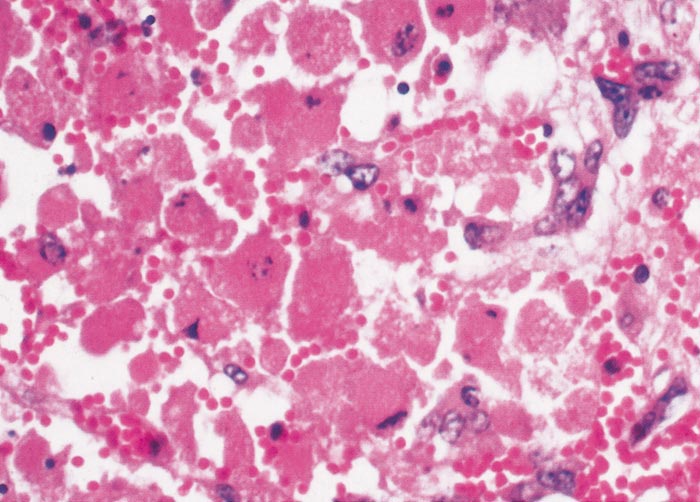

Lesions in target organs such as the liver in the acute disease are produced by the direct lytic effect of the virus on infected cells. In the liver of new-born lambs, for instance, there is initial cloudy swelling and hydropic degeneration of randomly scattered hepatocytes, which soon become necrotic as manifested by acidophilic cytoplasm and pyknotic nuclei. The lesions rapidly progress to form scattered primary necrotic foci of five to eight affected hepatocytes, with the presence of acidophilic cytoplasmic or apoptotic bodies resulting from cytolysis, and infiltration of neutrophils. As the primary lesions enlarge, numerous degenerated and necrotic hepatocytes and acidophilic bodies appear throughout the parenchyma. Ultimately there is massive necrotic hepatitis in which the residual primary foci can still be recognized as dense aggregates of cellular debris infiltrated by leukocytes.117, 168

The haemostatic derangement that occurs in RVF has been investigated in detail only in rhesus monkeys, and the mechanisms involved remain speculative.125, 497 Impairment of coagulation occurs even in benign infection in monkeys,125, 497 and it is notable that moderate thrombocytopenia has been observed in benign infection in sheep.595 However, haemostatic derangement is most severe in the fatal hepatic syndrome, which manifests as a viral haemorrhagic fever with bleeding tendency and evidence of disseminated intravascular coagulopathy.125 Viraemia is intense and prolonged in individuals that develop the haemorrhagic syndrome, indicating that there is impaired clearance of viraemia and extensive dissemination of virus with attendant widespread tissue damage, and it is postulated that the critical lesions in the development of the haemorrhagic state are vasculitis and hepatic necrosis.125, 497, 498 Destruction of the antithrombotic properties of endothelial cells is thought to trigger intravascular coagulation, and the widespread necrosis of hepatocytes and other affected cells to result in the release of procoagulants into the circulation. Severe liver damage presumably limits or abolishes production of coagulation proteins and reduces clearance of activated coagulation factors, thereby further promoting the occurrence of disseminated intravascular coagulopathy, which in turn augments tissue injury by impairing blood flow. Vasculitis and haemostatic failure result in purpura and widespread haemorrhages.